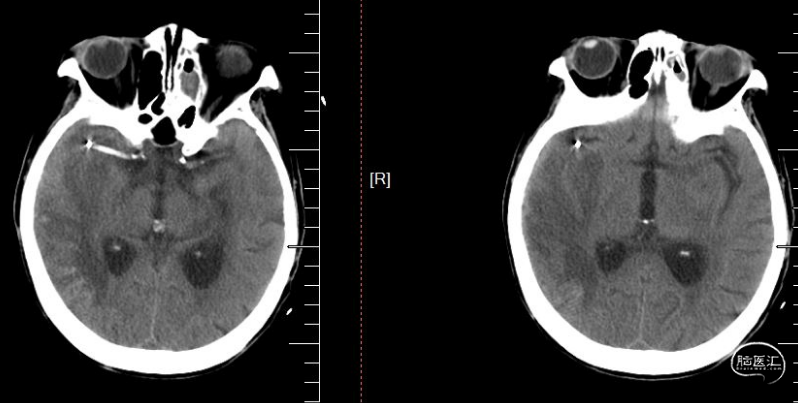

术前影像

术前CT, Aspects评分5分

术后24小时CT。

术后7天CT。